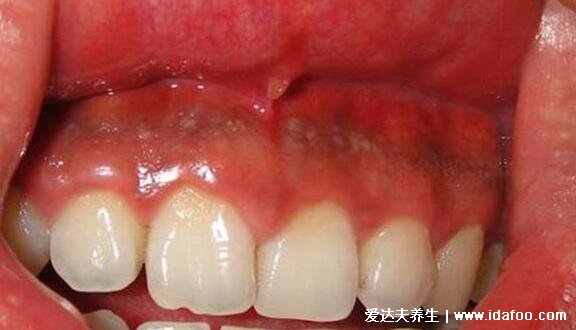

早期牙龈炎图片及症状

1、牙龈出血

很多牙齿疾病都会出现这种症状,一般有满性牙龈炎的患者刷牙或者咬硬物的时候会有出血症状,一般不会有没有原因的出血情况,有的患者会伴随牙龈局部痒、肿胀、口臭等......